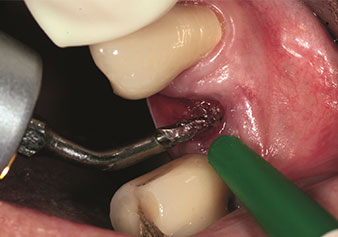

One application, which is often underestimated is the atraumatic extraction of tooth roots or root fragments in the scope of alveolar management. The fine periotomes, which are currently available in two versions (EX1 and EX2 from W&H), can also be used to remove teeth which have previously undergone special endodontic treatment or ankylosed roots with ease. This results in extraction alveoli where both the hard and soft tissue are fully intact as it is generally possible to avoid reflection.

This establishes the optimal basis for subsequent or immediate implant treatment (Figures 1 and 2 included with the kind permission of Dr Torsten Conrad, Bingen a. Rhein).